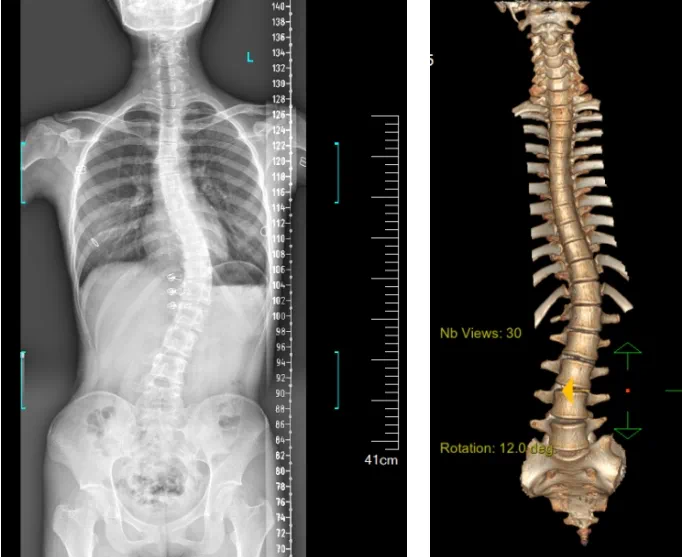

患者為一名16歲女孩,發現脊柱側彎1年,到南方醫院贛州醫院脊柱外科求診。經查體,患者左右胸廓不對稱,雙肩等高,左肩胛骨隆起,背側呈“剃刀背”畸形,胸腰段棘突偏離正中線,胸腰段脊柱左側凸畸形;各棘突無壓痛及叩擊痛,右側腰部凹陷,胸腹及腰背部感覺正常。檢查發現患者特發性脊柱側彎,Lenke5C型,主胸彎51°。患者及家屬對外觀不滿意,為改善外觀及功能,要求手術矯形治療。

據悉脊柱側彎手術治療后可以保持軀干平衡,改善外觀并防止畸形進一步發展。患者的生活質量得到提高,進而減少脊柱過度畸形可能帶來的疾病的發生率,外觀上的積極變化往往也能帶來患者心理與精神的積極變化。臨床上會綜合考慮患者的年齡、側彎程度、進展趨勢、骨質條件、鄰近節段情況、手術節段等因素,合理采用個性化的手術方式進行治療。然而,由于脊柱神經血管密布,手術操作相對復雜,手術難度高、風險大,傳統脊柱側彎的手術方式往往有較高的神經或脊髓損傷風險。故此次科室決定開展機器人輔助導航下脊柱側彎矯形、植骨融合內固定手術。術前,醫生團隊在機器人多維度圖像融合智能手術規劃功能的輔助下,預先規劃了理想的置釘路徑。術中,天璣骨科手術機器人準確遵循術前規劃,根據配準結果,實時定位并準確執行置釘操作,所有導針均用電鉆置入,一次性成功,協助醫生順利完成手術。最終,在麻醉科、手術室密切配合下,歷時3小時成功完成側彎矯形術,出血量僅500ml。術后,患者恢復良好,大小便及下肢神經運動感覺正常。